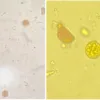

Cinco pacientes (10,6%) apresentaram o que os autores chamaram de “fenótipo fibrótico”, caracterizado pelo espessamento do septo alveolar – estrutura onde ocorrem as trocas gasosas. Ou seja, nesses indivíduos o tecido normal do pulmão lesionado pelo vírus foi substituído por tecido cicatricial (fibrose), o que dificultou a respiração. Em outros dez pacientes (21,2%), classificados como “fenótipo trombótico”, o tecido pulmonar estava praticamente normal. Porém, foi possível notar sinais de coágulos (trombos) em pequenos vasos. Há ainda um terceiro grupo no qual foram incluídos 32 pacientes (68,1%) que apresentaram os dois fenótipos simultaneamente.

As amostras pulmonares foram obtidas por meio de autópsia minimamente invasiva e, depois, fixadas em formol e parafina. Os blocos foram então cortados em lâminas com espessura de 3 micrômetros (µm, o equivalente a um milionésimo de metro), que foram coradas e analisadas por microscopia e imuno-histoquímica (técnica que envolve o uso de anticorpos contra proteínas-alvo, por exemplo, o colágeno). O RNA do SARS-CoV-2 foi identificado em todas as amostras por meio de RT-PCR.

No artigo, os autores relatam que, nos dias que antecederam o óbito, os pacientes com o fenótipo fibrótico sofreram um declínio progressivo no índice de oxigenação – medido pela relação entre pressão parcial de oxigênio arterial com a fração inspirada de oxigênio (PaO2/FiO2) –, além de perda da complacência pulmonar (capacidade do órgão de expandir e retrair durante a respiração) e aumento na produção de colágeno (um dos principais componentes do tecido fibrótico) no órgão.

Já nos pacientes do grupo trombótico foi relatada uma melhora nos padrões respiratórios nos dias anteriores à morte, bem como alto nível de complacência pulmonar durante todo o período de hospitalização. “Em alguns casos, o médico relatou que chegaram perto de ter alta e, logo em seguida, faleceram”, conta Fabro.

Por outro lado, os doentes desse segundo grupo apresentavam elevação no nível de plaquetas (células sanguíneas envolvidas na formação de coágulos) e na formação de trombos. Além disso, observou-se que, no momento da admissão hospitalar, eles tinham níveis mais alto de dímero-D – proteína considerada um marcador de trombose – do que a média dos pacientes analisados.